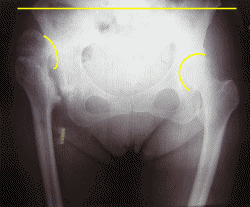

立った状態で、右足(写真左)が25mm高くなっている靴を履いています。

■左右の股関節の形状・位置が異なっています。

骨盤は傾いていますが、腰の骨5番は、水平を保っているのが診られます。

腰の骨5番の水平を保つように、靴の高さを調整してきました。